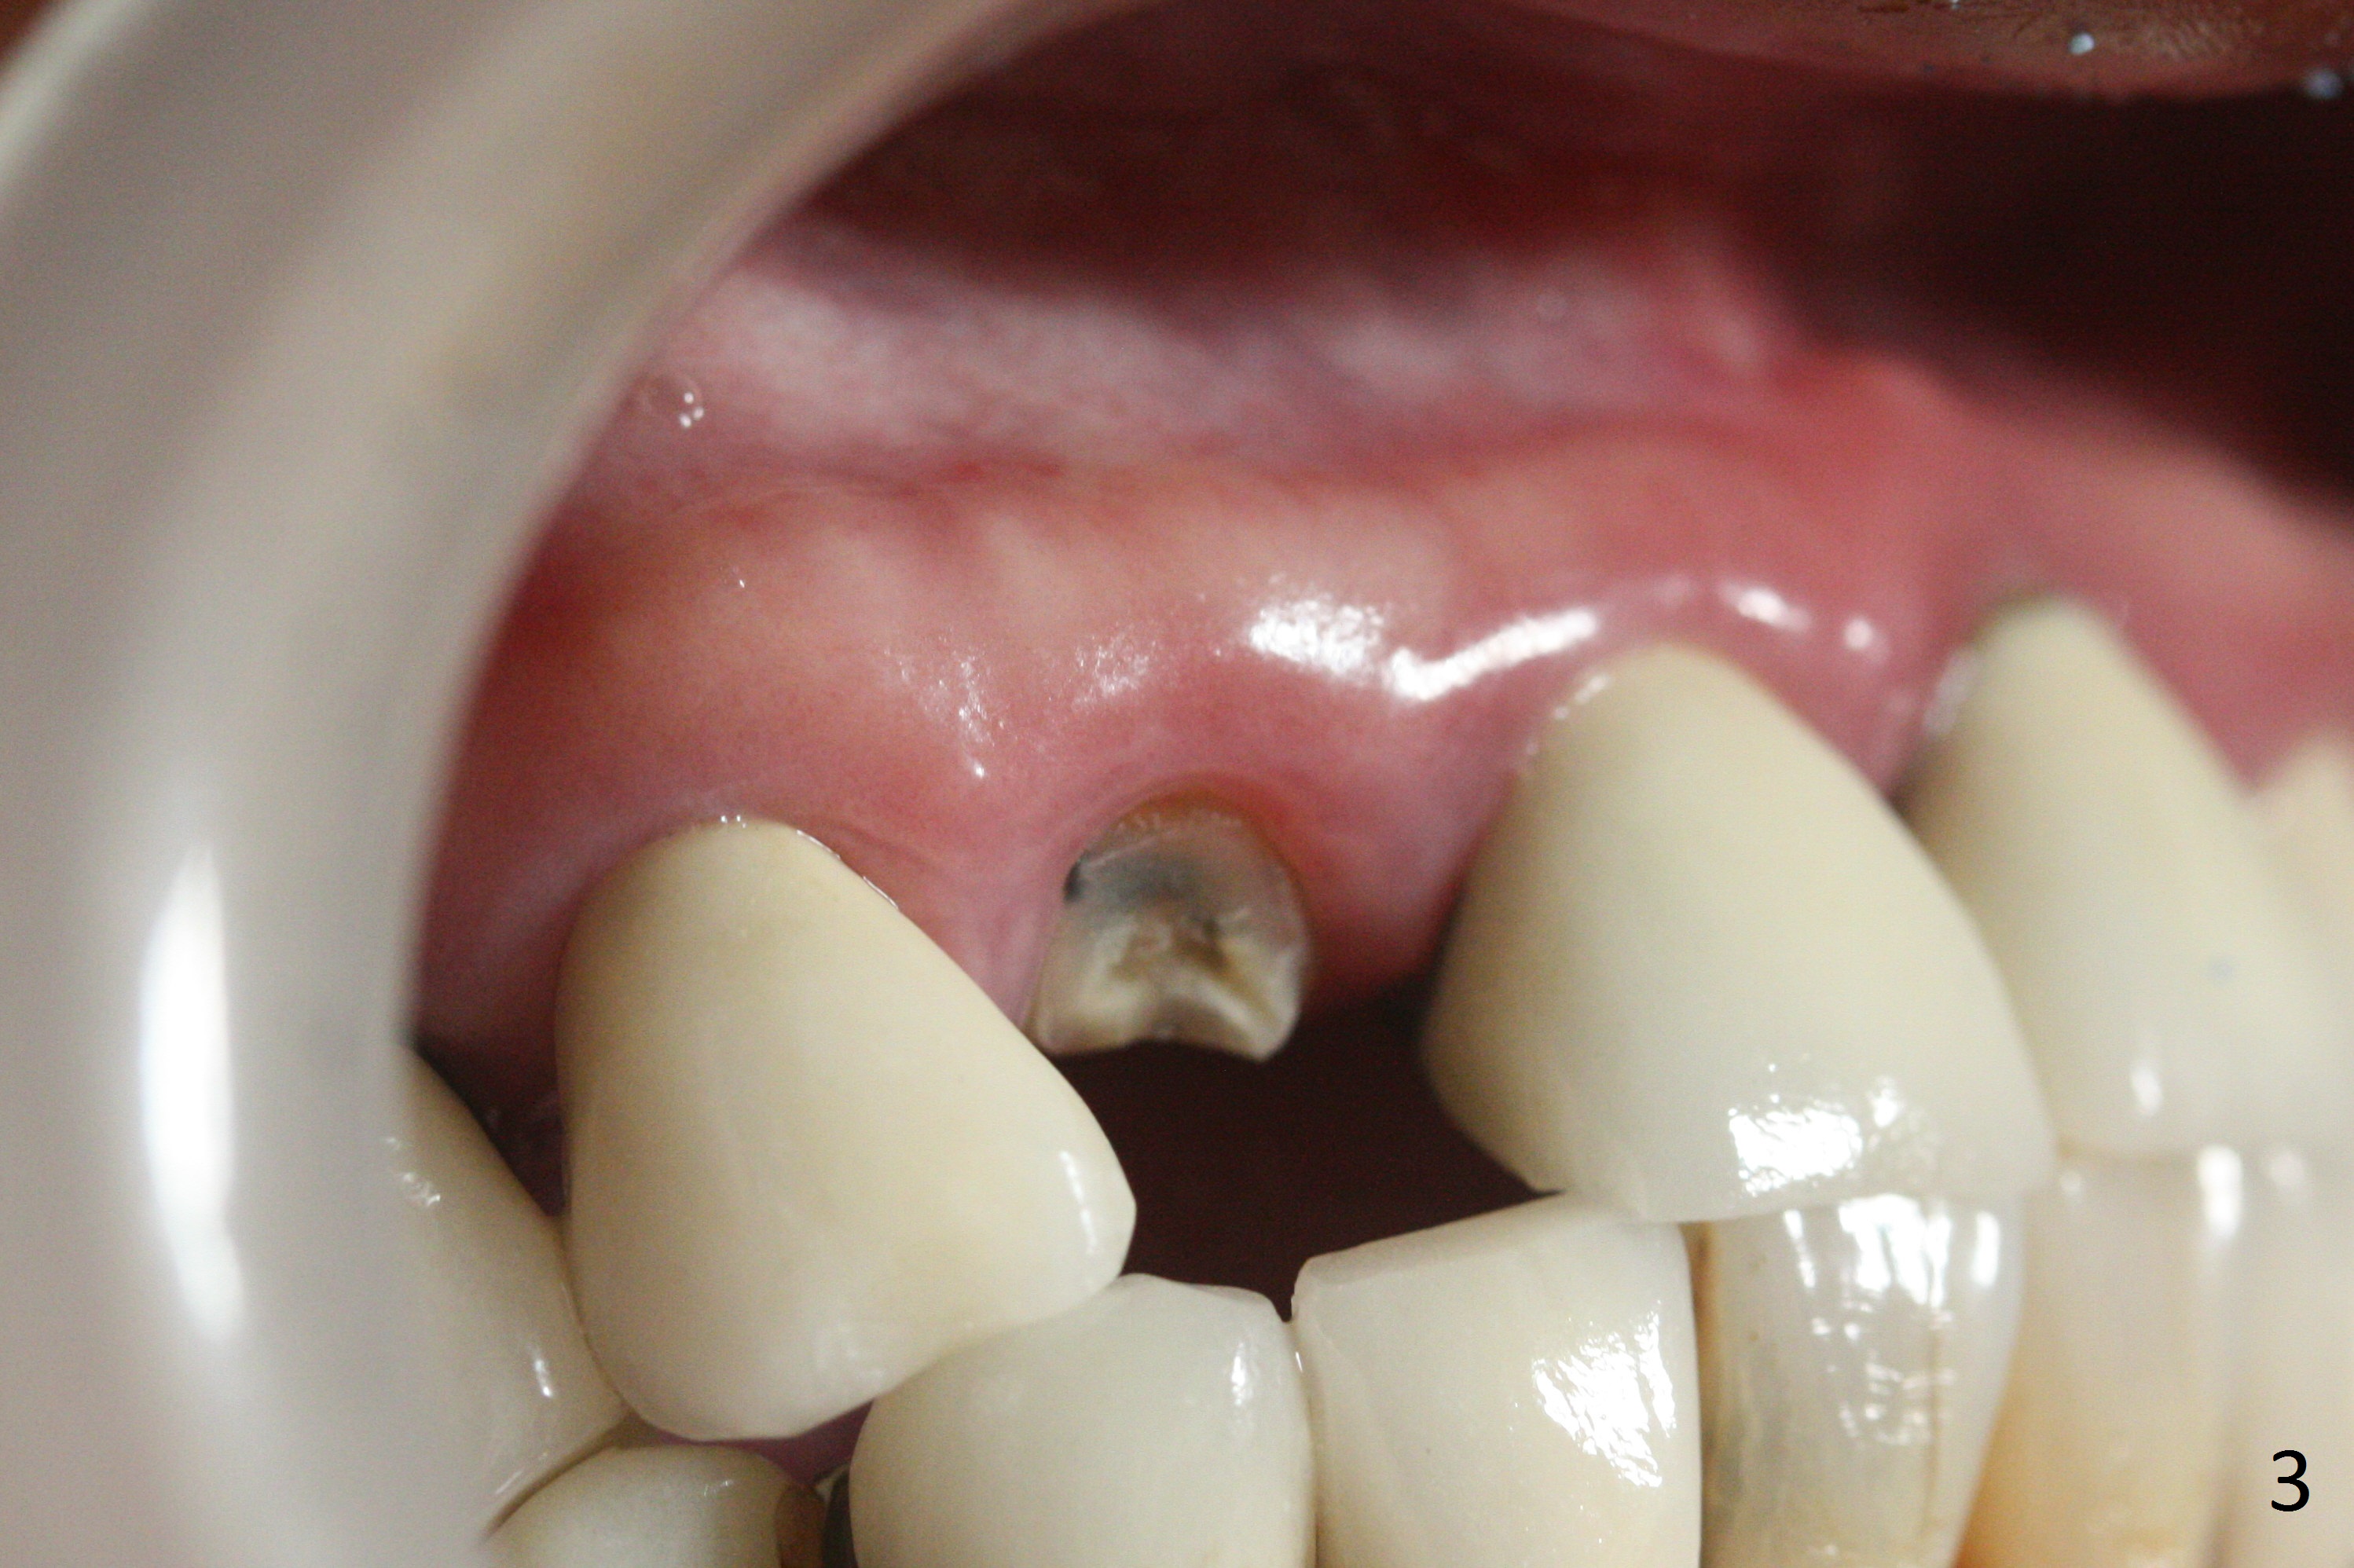

In fact the residual root (Fig.3) is easy to remove. A 3.8x16 mm implant is placed (Fig.4 (with 2 mm buccal gap)) at the level as planned (Fig.2). Insertion torque is acceptable. After placing a 4.5x5(3) mm gold-coated abutment and allograft (Fig.5), an immediate provisional is fabricated (the existing crown is lost). The patient is pleased with the quick, painless procedure.